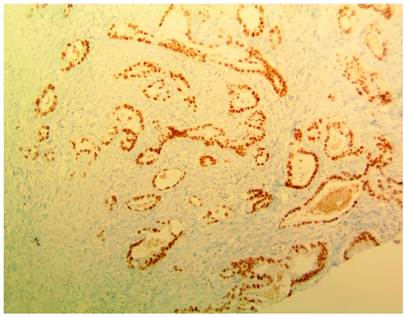

En hospital de remisión requirió manejo con apendicectomía laparoscópica y derivación de vía biliar por colangiopancreatografía retrógrada endoscópica, con inserción de un stent biliar. Hallazgo intraquirúrgico de un plastrón apendicular, abundante líquido peritoneal cetrino, estrechez del conducto hepático común, con sospecha de compromiso neoplásico. Se trasladó al Hospital Militar Central en Bogotá, Colombia, para continuar con manejo integral. Se documentó síndrome biliar obstructivo, con recuento de bilirrubina total de 3,02 mg/dL, bilirrubina directa de 2,71 mg/dL, fosfatasa alcalina de 1006 UI/L, alanina aminotransferasa (ALT) de 149 U/L y aspartato aminotransferasa (AST) de 139 U/L. Los hallazgos de la colangiorresonancia se exponen en la Figura 1 y los de la tomografía axial computarizada (TAC) en la Figura 2. El resultado de la biopsia apendicular evidenció compromiso por adenocarcinoma moderadamente diferenciado de serosa y capa muscular (Figura 3), con inmunohistoquímica positiva para anticuerpos CK7, EMA, CEA monoclonal y CDX2 (Figura 4), que sugirió origen extraapendicular, probablemente de tracto gastrointestinal superior o hepatobiliar.

Figura 3 Hallazgos microscópicos del espécimen quirúrgico. Tinción de hematoxilina y eosina, que muestra múltiples células tumorales, que infiltran la capa serosa apendicular hasta la submucosa.